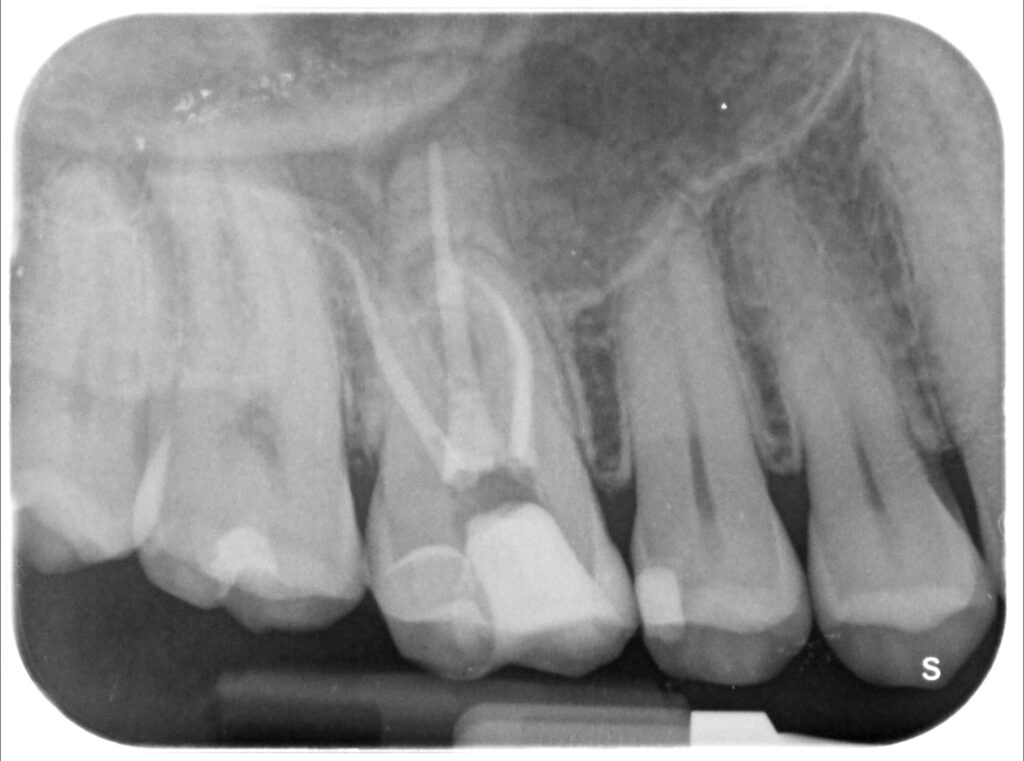

Caso clinico – trattamento ortogrado 1° molare superiore con lesione